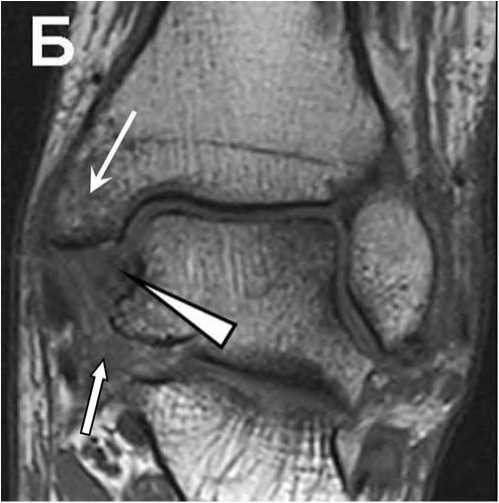

Рис. 8. Т1 TSE Томограммы в коронарной проекции пациента с жалобами на боль в голеностопном суставе без анамнеза острой травмы.

А: В своде блока таранной кости определяется участок формирования костного фрагмента, покрытый суставным хрящом (обычная стрелка).

Б: Тот же пациент, через 1 месяц. Отмечается перелом суставного хряща в Медиальном отделе, нестабильность фрагмента с небольшим смещением (треугольная стрелка).